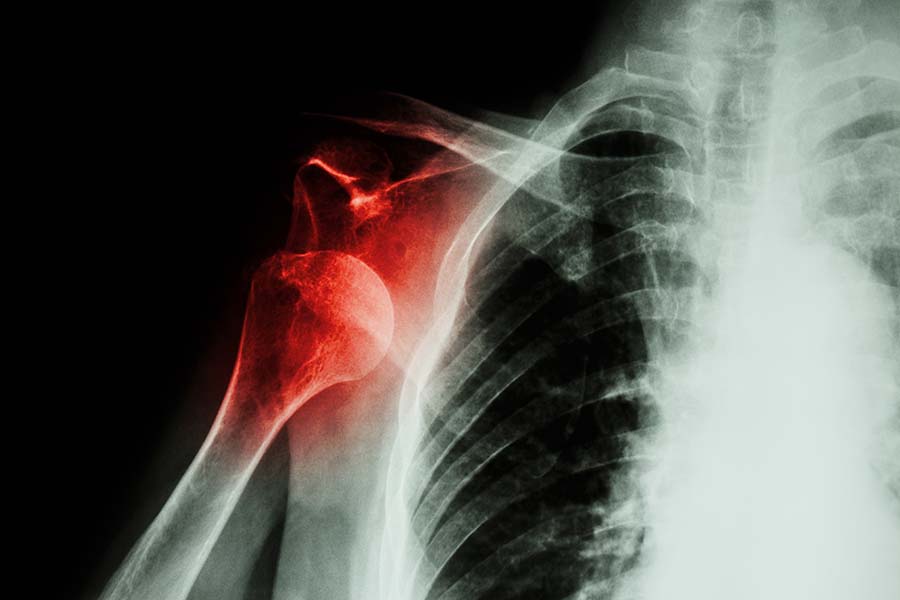

Does your shoulder pop in and out of the socket easily? You are not alone. Recurrent shoulder subluxation is common with previous history of shoulder dislocation. And the shoulder joint is the most frequently dislocated joint in the body.

Our shoulder is a ball and socket joint, built like a joystick. However, our shoulders need to move through a much bigger range than the common joysticks. To achieve this, the socket of the shoulder joint is designed to be small. As a result, the shoulder joint is inherently unstable.

First-time shoulder dislocation is usually caused by trauma, such as a fall or impact on the shoulder during sports. A shoulder dislocation is defined by the ball of the joint coming completely out of the socket. It usually has to be put back into place by a doctor. Both the muscles and ligaments around the shoulder, and sometimes even the bony structures can be injured during a shoulder dislocation, therefore weakening and overstretching the structures that maintain the stability of the shoulder.

Now you can see, why once a shoulder has dislocated, it is more prone to develop recurrent dislocation and subluxation in the future. Subluxation is a partial dislocation where the ball of the joint comes partially out of the socket. You will be able to relocate the shoulder joint easily in a case of subluxation.